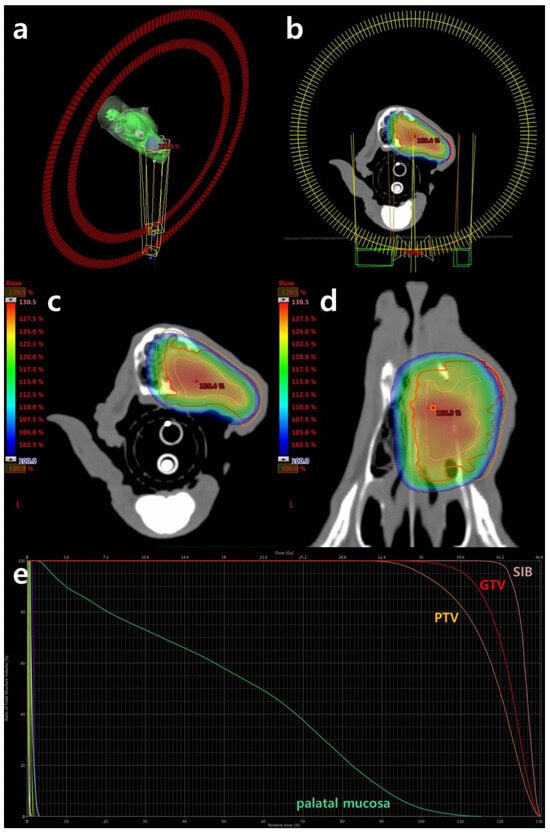

Despite the recommendation for surgical excision, the owner declined due to concerns regarding its invasiveness. Instead of surgical removal, palliative radiotherapy was chosen to control hemorrhage and improve quality of life. Volumetric modulated arc therapy (VMAT) was administered using a 6 MV linear accelerator (clinic iX, Varian Medical Systems, Inc., Palo Alto, CA, USA) equipped with a 5 mm leaf width multileaf collimator (MLC). Inverse treatment planning was conducted using the Varian Eclipse treatment planning system (Eclipse™ version 13.7.33, Varian Medical Systems, Inc., Palo Alto, CA, USA) utilizing two 360° volumetric arcs (Figure 3). The prescribed dose was 36 gray (Gy), delivered in six fractions of 6 Gy each weekly. Given the patient’s severe hemorrhagic anemia before radiotherapy, two treatments were administered in the first week to achieve rapid hemostasis, resulting in a total treatment duration of 5 weeks. The gross tumor volume (GTV) was delineated as the contrast-enhanced lesion observed in CT images. To deliver a dose of 120% at the center of the GTV, a 3 mm isotropic volume within the GTV was designated as the simultaneous integrated boost (SIB). The planning target volume (PTV) included a 3 mm isotropic expansion from the GTV. The dosimetric objectives were aimed at 100% prescription dose coverage of 99% of the GTV and 95% of the PTV (Figure 3). The organs at risk (OAR) included the eyes, lenses, optic nerves, optic chiasm, brain, and palatal mucosa. Quality assurance was performed using gamma analysis with the Varian portal dosimetry system on individual fields, with a minimum of 95% gamma for a 3 mm distance to agreement and a 3% absolute dose difference defined as passing the quality assurance criteria. The volumes of target structures and calculated radiation doses/volumes to those structures are summarized in Table 1.

Figure 3. Radiation planning computed tomography scans using Varian EclipseTM (version 13.7.33) planning software: (a,b) the arcs encircling the oral mass illustrate the trajectory of the 360° volumetric arcs employed for radiation delivery, with one arc moving clockwise and the other counterclockwise; (c,d) the figures display the simultaneous integrated boost (SIB, pink), gross tumor volume (GTV, red), and planning target volume (PTV, orange) superimposed with the estimated radiation dose represented in color wash. It exclusively delineates regions receiving the prescribed dose (36 gray) or higher, with the red dot denoting the maximum hot spot for this slice; (e) the dose–volume histogram delineates targets and organs at risk, including SIB (pink), GTV (red), PTV (orange), and palatal mucosa (green). The histogram indicates that 99% of the GTV and 95% of the PTV are covered by at least 36 gray.